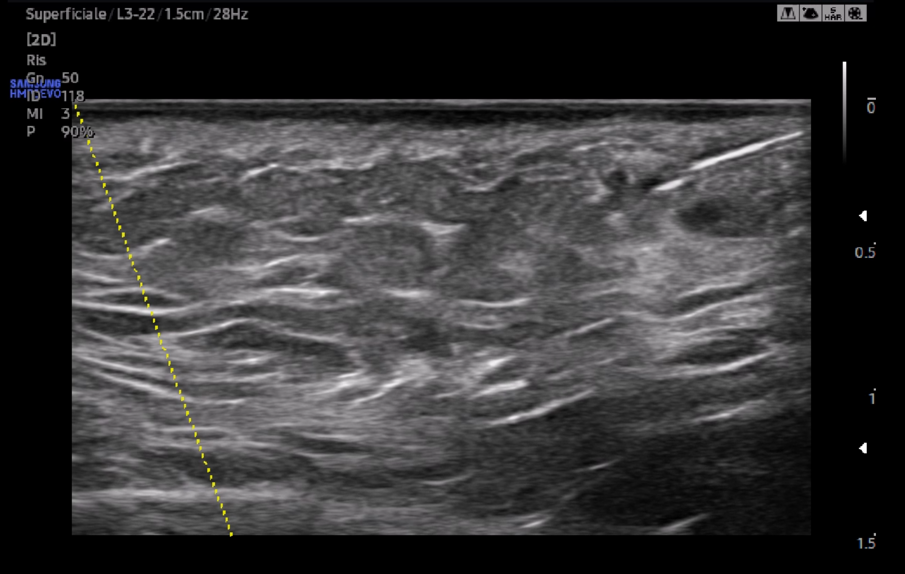

Gli ultrasuoni forniscono immagini in tempo reale con accuratezza variabile e dipendente dalle capacità dell’operatore e dalle potenzialità dell’apparecchiatura ecografica per uno studio accurato della cute e degli strati più superficiali del volto ma nascosti dall’epidermide (Fig. 1). Consentono una mappatura precisa delle strutture vascolari a prescindere dalle loro varianti anatomiche ed una valutazione della motilità dei piani muscolari. Ciò significa che con l’esame ecografico è possibile passare dall’osservazione anatomica statica a quella dinamica e valutare le straordinarie differenze ai fini diagnostici, esecutivi e post-operatori (Fig. 2) (clicca QUI e guarda il video). A causa della crescente popolarità delle procedure estetiche mininvasive al volto mediante tecniche iniettive/infiltrative/implantari, l’esame ecografico facciale è diventato fondamentale per tracciare i prodotti iniettabili, prevenire complicanze e, se necessario, riconoscerle per intervenire tempestivamente. Eventi avversi possono verificarsi al momento dell’iniezione, come le occlusioni o le compressioni vascolari, subito dopo il trattamento, come le infezioni, o diversi mesi dopo, come la comparsa di reazioni nodulari infiammatorie. Eseguire una metodica estetica al volto, sia essa infiltrazione di filler, iniezione intramuscolare di tossina botulinica o impianto di fili di trazione o di biostimolazione, sotto guida ecografica, fornisce un riscontro dinamico contestuale del posizionamento del riempitivo, consentendo al clinico di operare nell’area anatomica prescelta evitando sconfinamenti indesiderati (clicca QUI e guarda il video).

L’incidenza di complicanze vascolari dopo le iniezioni di filler pare essere 1/6600 (0,015%). Tuttavia, sebbene questo rischio non sembri molto elevato, anche un operatore esperto può incorrere in questo evento avverso. Se, da un lato, gli ultrasuoni possono aiutare nell’identificare e valutare il decorso dei vasi sanguigni a rischio di occlusione o compressione (Fig. 3), dall’altro, in caso di evento avverso correlato al filler a base di acido ialuronico, l’enzima ialuronidasi può essere iniettato con la guida degli ultrasuoni esattamente nel deposito del prodotto per una sua mirata dissoluzione (Fig. 4). Con l’avanzare dell’età, l’immagine della cute si modifica sia negli spessori sia nel numero degli annessi. L’esame ecografico contribuisce a visualizzare il progressivo deterioramento cutaneo: un assottigliamento del derma, la riduzione delle fibre collagene, la degenerazione delle fibre di elastina e la disidratazione influiscono sull’ecogenicità dei tessuti esaminati (Fig. 5).

Fig. 1

Fig. 2

Fig. 3

Fig. 4

Fig. 5